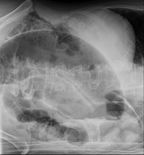

CT scan of a small bowel volvulus. It shows two juxtaposed segments of narrowing, which is the spot of mesentery rotation. The other signs indicate strangulation.